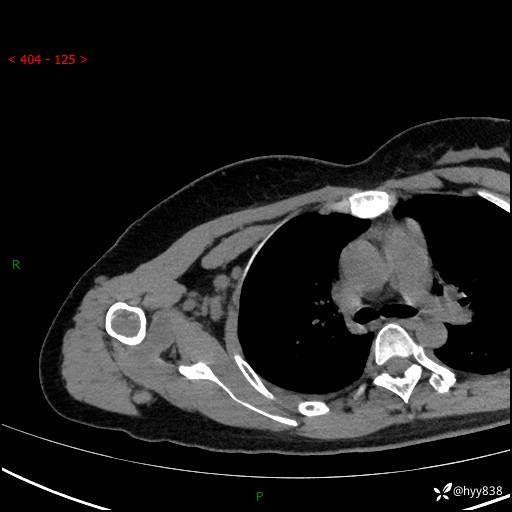

中年女性,发现右肩关节占位2天。有特征、有细节---结果公布~

年龄:47岁

主诉:发现右肩关节占位2天

现病史:患者3年前摔伤致右肩部疼痛,未行特殊处理,后右肩活动时轻度疼痛,患者未引起重视。1月前上述症状加重,于当地县人民医院就诊,2023-07-10右肩关节MR:右肱骨头、肩胛骨及周围软组织异常信号。现患者右肩可触及质硬包块,活动时疼痛,无头晕头痛、恶心呕吐、腹痛腹胀等,为求进一步治疗,来我科就诊,门诊以“右股骨占位性病变”收入我科。 起病以来,患者精神、饮食、睡眠可,大小便正常,体力、体重未见明显变化。

右肩关节CT平扫